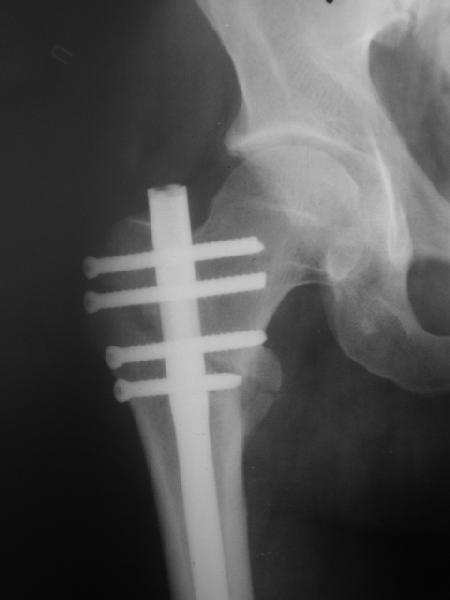

> При межвертельных переломах с цефаломедуллярными гвоздями бывает,

> что проксимальый винт проходит или черед периферический отломок, или

> прямо над ним. И если остался диастаз, то этот винт при осевой

> нагрузке не дает сблизиться отломкам. Пример остеосинтеза в застарелом

> случае в приложении. В качестве предупреждающей меры можно долотом

> разрушить латеральную стенку дистального отломка под винтом.

Полностью с Вами согласен! Хотя можно поставить блокирующий винт и под углом 90 град. - как в бедренных гвоздях, были бы они потолще!

Конечно, мы не синтезируем остеопорозые вертельные переломы согласно прилагаемому примеру, винты 6 мм вырежутся. Но у более молодых при хорошем качестве кости такие или подобные гвозди с поперечным расположением винтов вполне применимы для меж- и подвертельных переломов.